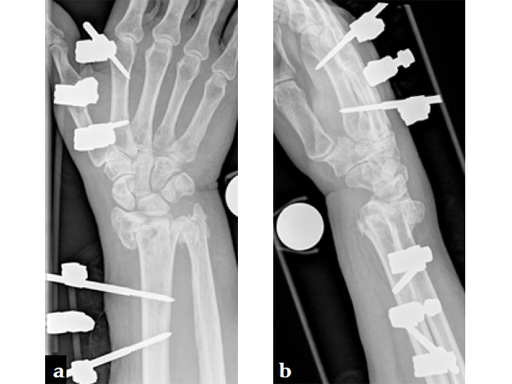

Fig 2ab Initial management was with closed reduction and joint bridging external fixator. There was loss of primary reduction due to inadequate positioning of the external fixator (too lateral).